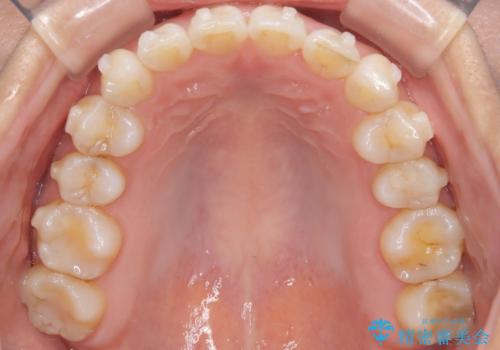

治療はインビザラインを使用し、1~2週間ごとに新しいマウスピースに交換しながら段階的に歯を移動させていきました。特に上下の正中が揃うよう、奥歯や前歯の位置関係に注意を払いながら細かく設計を調整。途中の確認でも、左右のバランスが取れてきたことをご本人も実感されていました。

治療期間は約1年半で、ガタついていた歯列はきれいに整い、上下の前歯の真ん中もぴったりと揃えることができました。透明なマウスピースのため周囲に気づかれず治療が進み、快適に続けられたとの感想もいただいています。